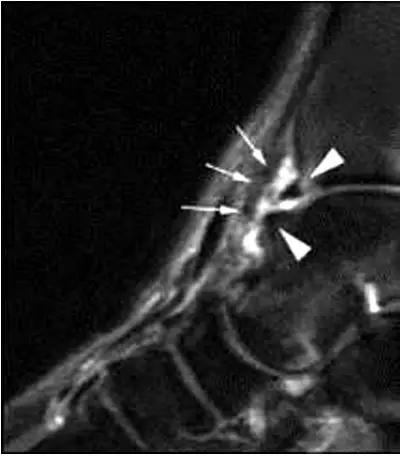

影像学表现为距骨胫骨间肌腱及趾长屈肌腱水肿、增厚,内踝及距骨后内侧骨赘形成。

轴位示意图示后内侧撞击综合征:M:内踝;L:外踝;TP:胫后肌腱;FDL:趾长屈肌腱;Talus:距骨。短箭:距骨胫骨间肌腱深层纤维;箭头:距骨胫骨间肌腱后部纤维。

X线平片示胫骨后部骨赘形成,MR质子像黑箭示胫骨内后侧骨赘形成,白箭示内后侧软组织增厚, 白箭头:胫后肌腱;黑箭头:趾长屈肌腱